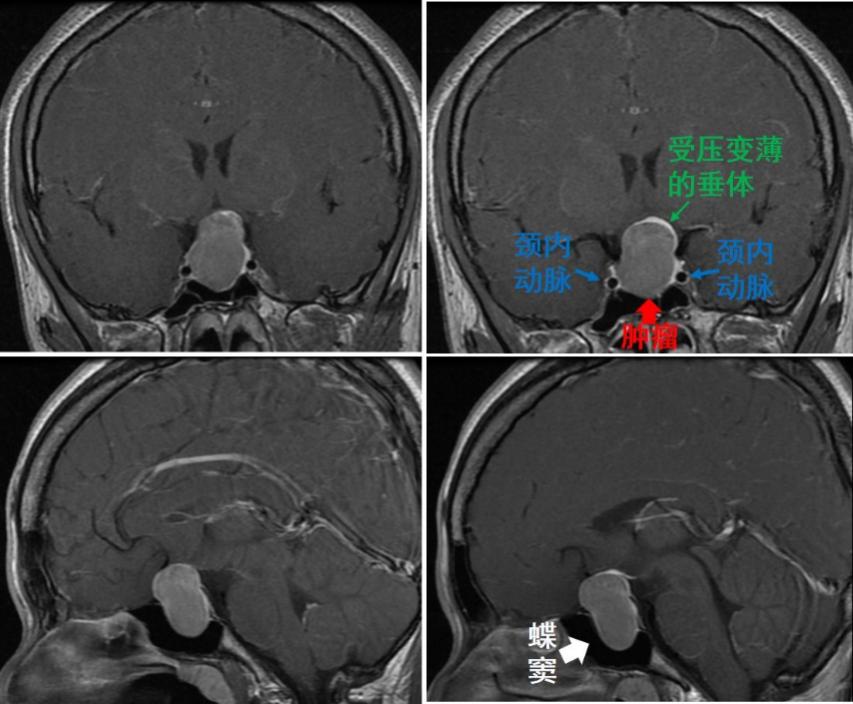

随后的磁共振进一步检查发现,她的颅内深部有一个近3厘米的垂体瘤,视神经和正常垂体明显受压。

▲ 磁共振检查发现鞍区肿瘤约3公分